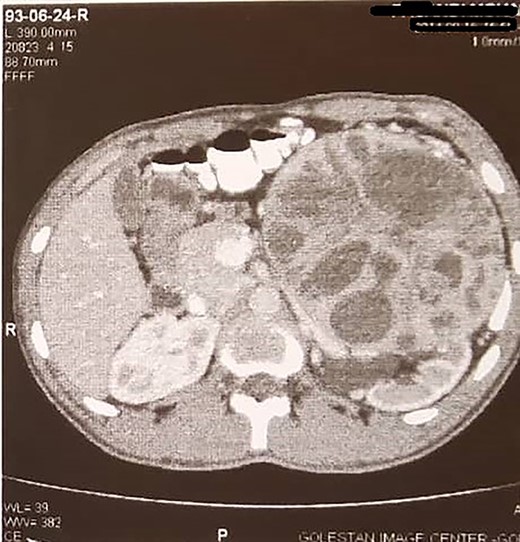

A 22-year-old man was referred to our clinic with ambiguous abdominal pain radiating to the left flank. The patient had a history of diabetes mellitus from 3 years ago. Also, he had a familial history of renal failure due to bilateral renal mass resection in his father. The physical examination revealed a left flank mass. The laboratory tests, including renal function and liver tests, were routine except for microscopic hematuria. In contrast-enhanced abdominal computed tomography scan, huge left renal mass with contrast enhancement was a noticeable finding (Fig. 1). The patient was scheduled for radical nephrectomy, but due to the family’s history of bilateral renal tumor and concern of patients regarding contralateral tumors in the future, he refused to undergo radical nephrectomy. Due to the size of the tumor, we choose to perform open surgery. The operation was performed through a flank incision in the bed of the 12th rib. Despite the large tumor size, we approached the tumor extraperitoneal. During the surgery, we encountered a vast left renal mass. Initially, we released the ureter to avoid accidental injury, then obtained early access to the renal pedicle to control bleeding with a Satinsky clamp.